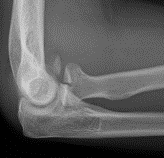

Coronal shear fracture of the distal humerus

Capitellum +/- trochlea

Type I Type II

Large osseous fracture of the capitellum

Articular cartilage injury with little bone

Hanh Steinthal fracture

Kocher Lorenz fracture

Double arc sign seen on xray

Double arc sign on xray